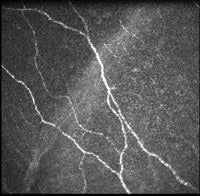

Thermal imaging of the eye

Ocular surface temperature has been observed for many years, but until recently the technology to observe the eye and the computing power to process the data limited the speed of assessment. Modern instruments produce a large amount of data, and the challenge is to find useful ways to manipulate this data. Our lab is using new imaging methods, coupled with the power of machine learning (AI), to develop new ways of looking at the eye using thermal imaging and of managing the data produced. We test our methods by investigating the change in ocular surface temperature in normal subjects, in contact lens wearers, in dry eye subjects, and as a tool to assess other instruments, such as an aesthesiometer or evaporimeter.